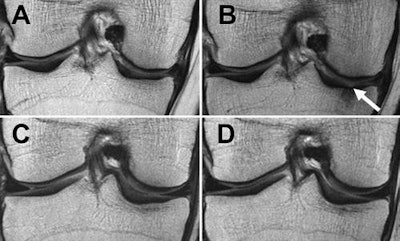

MRI scans of right knee at baseline (A and C) and after 48 months (B and D). Top-row images are of an obese 65-year-old woman with stable weight and mild knee pain; bottom-row images are of an obese 64-year-old woman with weight loss (11% less BMI) over 48 months. The woman with stable weight developed a full-thickness focal cartilage defect at the medial tibia (arrow). In contrast, no cartilage defects were seen in the woman with weight loss. Images courtesy of Radiology."These findings suggest that a larger amount of weight loss is more beneficial for cartilage than is moderate or no weight loss," the authors wrote. "Both weight loss groups showed reduced cartilage degeneration in the medial tibia, which supports the hypothesis that weight loss is most protective for the weight-bearing regions."